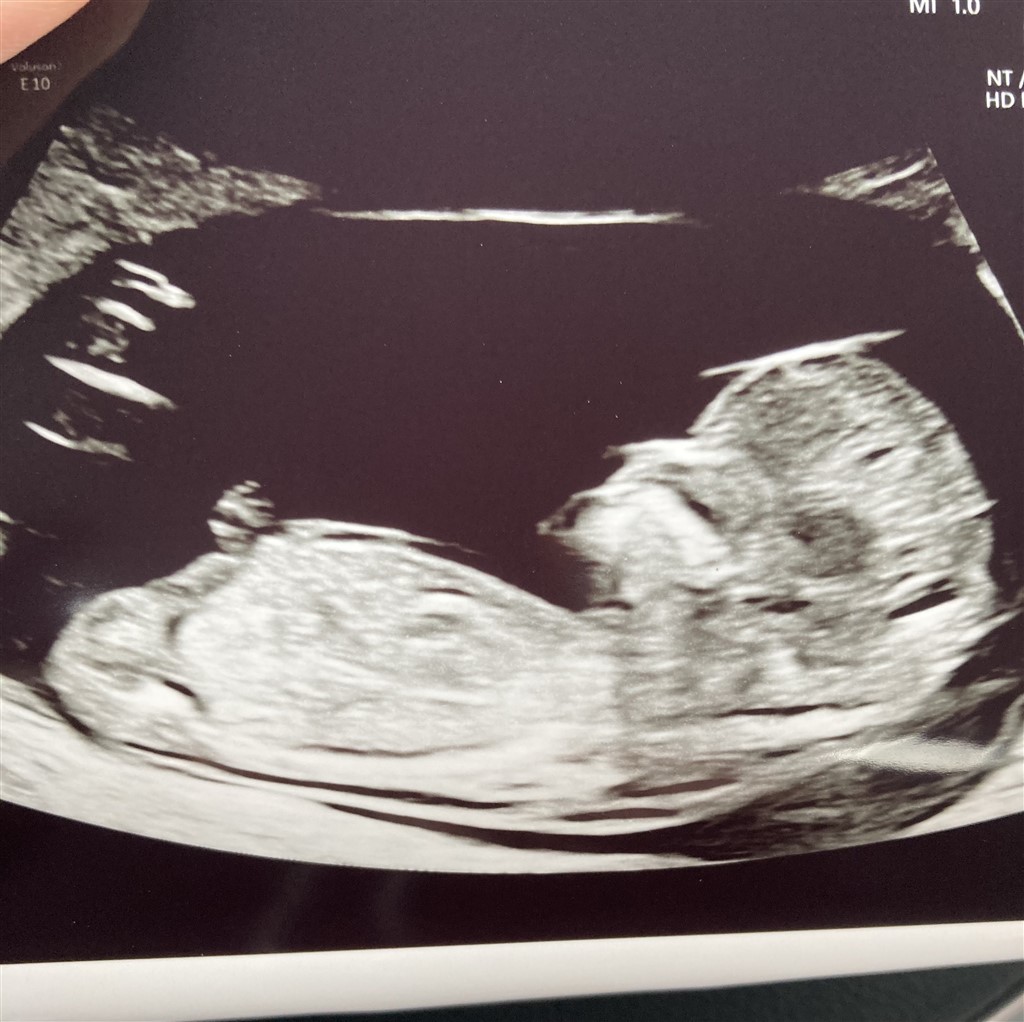

Ja så er der endnu en baby på vej. Bestemt ikke planlagt og lavet trods udebleven mens, men til verden dét vil den. Så velkommen det er den i hvertfald

Har været til nf som gik rigtig godt og måler baby til 12+5

Nogle gæt til hvad det kunne udvikle sig til?